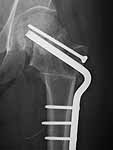

establish vascular status via mri and if viable follow with proximal valgus osteotomy

case provided s/p failed fixation

I think that this 31 yo deserves a try with valgus osteotomy, as so nicely illustrated by stephen kottmeier. However, I'd do it no matter what an MRI shows - thus why bother with the MRI? (What sort of data support MRI's ability to predict segmental collapse?)